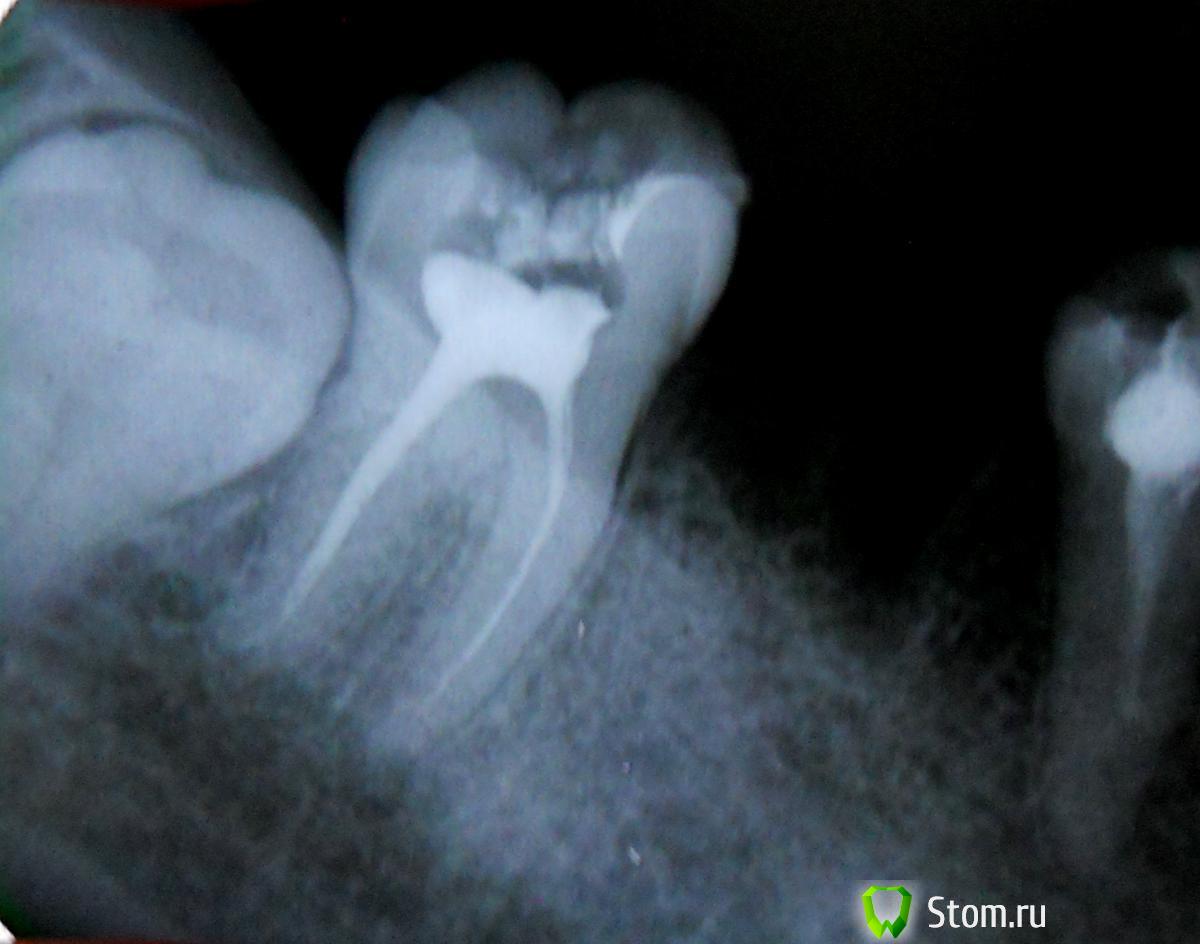

JOY Опубликовано 26 марта, 2012 Поделиться Опубликовано 26 марта, 2012 Добрый вечер! мне депульпировали 7 зуб на нижней челюсти...после пломбирования каналов терапевт отправил на рентген...Я заметила на правом корне на конце что то сомнительное...спросила,врач ответил, что это уплотнение в пределах нормы...но я сомневаюсь и прошу вашего совета. На данный зуб будет ставится мостовидный протез поэтому переживаю..может нужно полоскать или пропить антибиотики..мой врач уверяет, что ничего не нужно делать. Спасибо. Снимок прилагаю Ссылка на комментарий

DmitrySH Опубликовано 26 марта, 2012 Поделиться Опубликовано 26 марта, 2012 Кисты нет, но каналы обработаны не полностью. Рекомендовал бы повторную ревизию каналов. Иначе рано или поздно будут проблемы. Антибиотики, полоскания и тп не нужны. Ссылка на комментарий

FBR Опубликовано 26 марта, 2012 Поделиться Опубликовано 26 марта, 2012 Кисты нет, но каналы обработаны не полностью.Рекомендовал бы повторную ревизию каналов. Иначе рано или поздно будут проблемы. Антибиотики, полоскания и тп не нужны.гранулема на медиальном корне Ссылка на комментарий

Bier Опубликовано 26 марта, 2012 Поделиться Опубликовано 26 марта, 2012 да, гранулема есть. Надо сделать новый снимок и возможно переделать каналы. Ссылка на комментарий